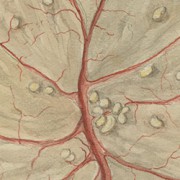

Lilly Ebstein Lowenstein (1897-1966) led a life between science and art, drawing and taking photographs in the fields of Medicine and Zoology. In her work, Lilly combined her technical knowledge of photography and drawing, the study of the sciences and a remarkable talent for aesthetics. She was born in Germany and studied at the Lette-Verein School in Berlin from 1911 to 1914. In 1925, she immigrated with her husband and two children to São Paulo. In 1926, she became an illustrator and photomicrographer at the Illustration and Photography Department at the School of Medicine (USP, as of 1934), which she headed for thirty years after 1932. Lilly collaborated at Instituto Biológico de Defesa Agrícola e Animal (the Biological Institute for the Defense of Agriculture and Animals), from 1930 to 1935, namely in the Avian Pathology Department. A life with art dedicated to the research and dissemination of science.